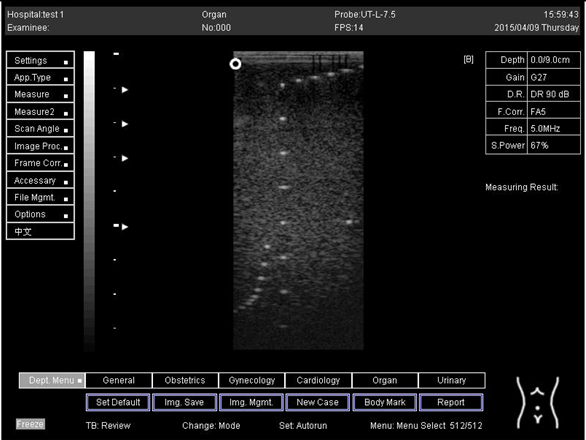

7.0 Biomimetics 07 00130 i035

9.0 Biomimetics 07 00130 i036